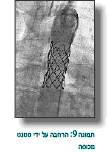

תומכנים

תומכנים עשויים מרשת סיבי מתכת. מלבישים אותם על בלון בגודל הרצוי ומרחיבים אותם באמצעות הבלון, והם נצמדים בלחץ לדפנות, מרחיבים ההיצרות ומונעים את החזרה (Recoil), וזה יתרונם לעומת הרחבה עם בלון בלבד. יש תומכנים חשופים ויש שמכוסים בחומר שאוטם אותם (תמונה 9) וכנראה מפחית את הסיכוי לקרע של אבי העורקים או נזק וחולשה לדופן והתבלטות בצורה של מפרצת (אנאוריזמה) (תמונות 10).